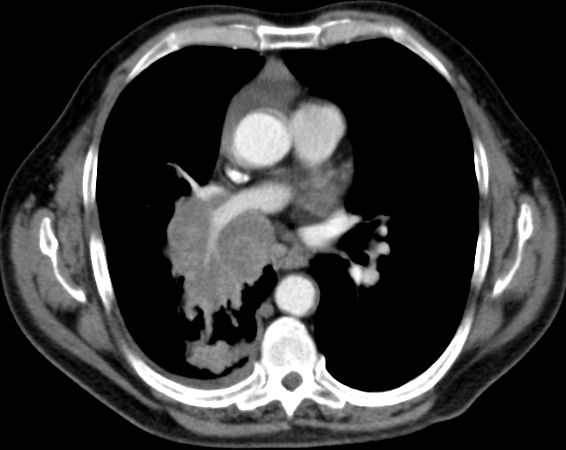

Kleinzelliges Bronchialkarzinom des rechten Hauptbronchus T4 N2 M1bra.

Kleinzelliges Bronchialkarzinom des rechten Mittellappens T3 N3 M0.